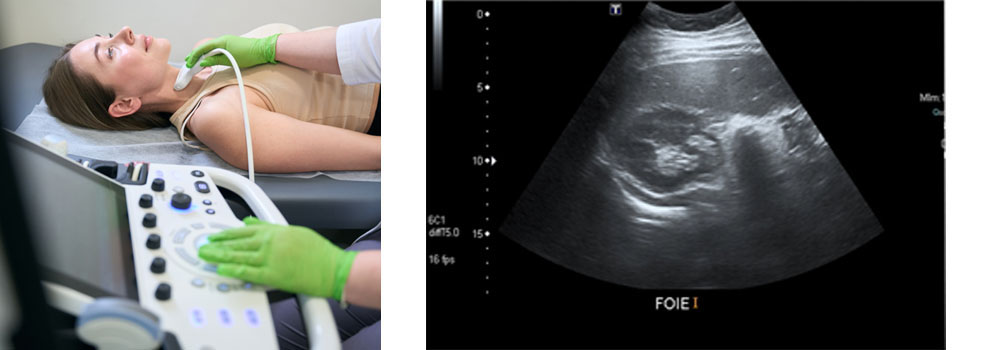

DIAGNÓSTICO POR ULTRASONIDOS. ECOGRAFÍA

Los estudios del cuerpo realizados con ultrasonidos por personal experto y un equipamiento avanzado, permiten la producción de imágenes de calidad de cualquier parte del cuerpo humano. Un examen de ultrasonidos utiliza una instrumentación denominada transductores, los cuales introducen en los tejidos del cuerpo ondas de sonido de alta frecuencia que detectan los ecos producidos cuando estas saltan sus estructuras internas. Los diferentes tejidos del cuerpo reflejan los ecos de forma diferente y un software específico genera imágenes que se visualizan en el monitor y son analizadas por el radiólogo. Leer más...

Pruebas diagnósticas efectuadas con ultrasonidos:

• Estudios de abdomen

• Estudios de vesícula

• Tiroides

• Mama

• Estudios del útero

• Vasos sanguíneos

• Estudios musculoesqueléticos